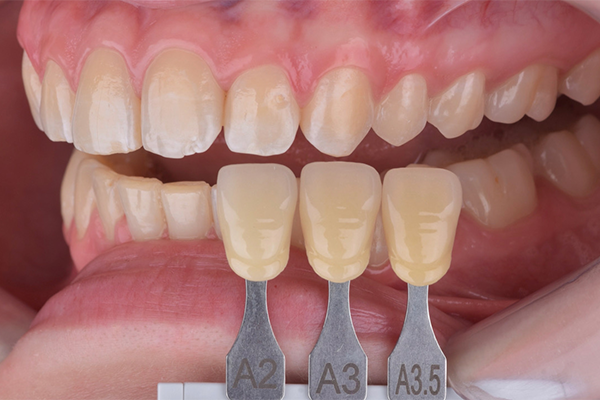

Na primeira consulta, foi realizada a profilaxia dos arcos dentários, com o objetivo de remover biofilme e facilitar a avaliação da coloração dental. Na consulta subsequente, foi realizada a mensuração da cor inicial dos dentes utilizando a escala de cor A-D. Foram identificadas as tonalidades A2 para os incisivos centrais superiores e A3 para os caninos superiores.

3 e 4 | Aspecto inicial, seleção de cor.